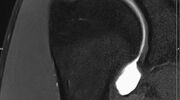

Gelenke

• Beurteilung von Knochen, Bändern und anderen Weichteilstrukturen der Gelenke nach Unfall.

• Arthrosediagnostik (Knorpelschaden)

• Impingement-Symptomatik

• Ursachenklärung bei wiederholter spontaner Gelenkluxation

• Ausbreitungsdiagnostik bei Gelenkentzündung, z.B. im Rahmen von rheumatischen Grunderkrankungen